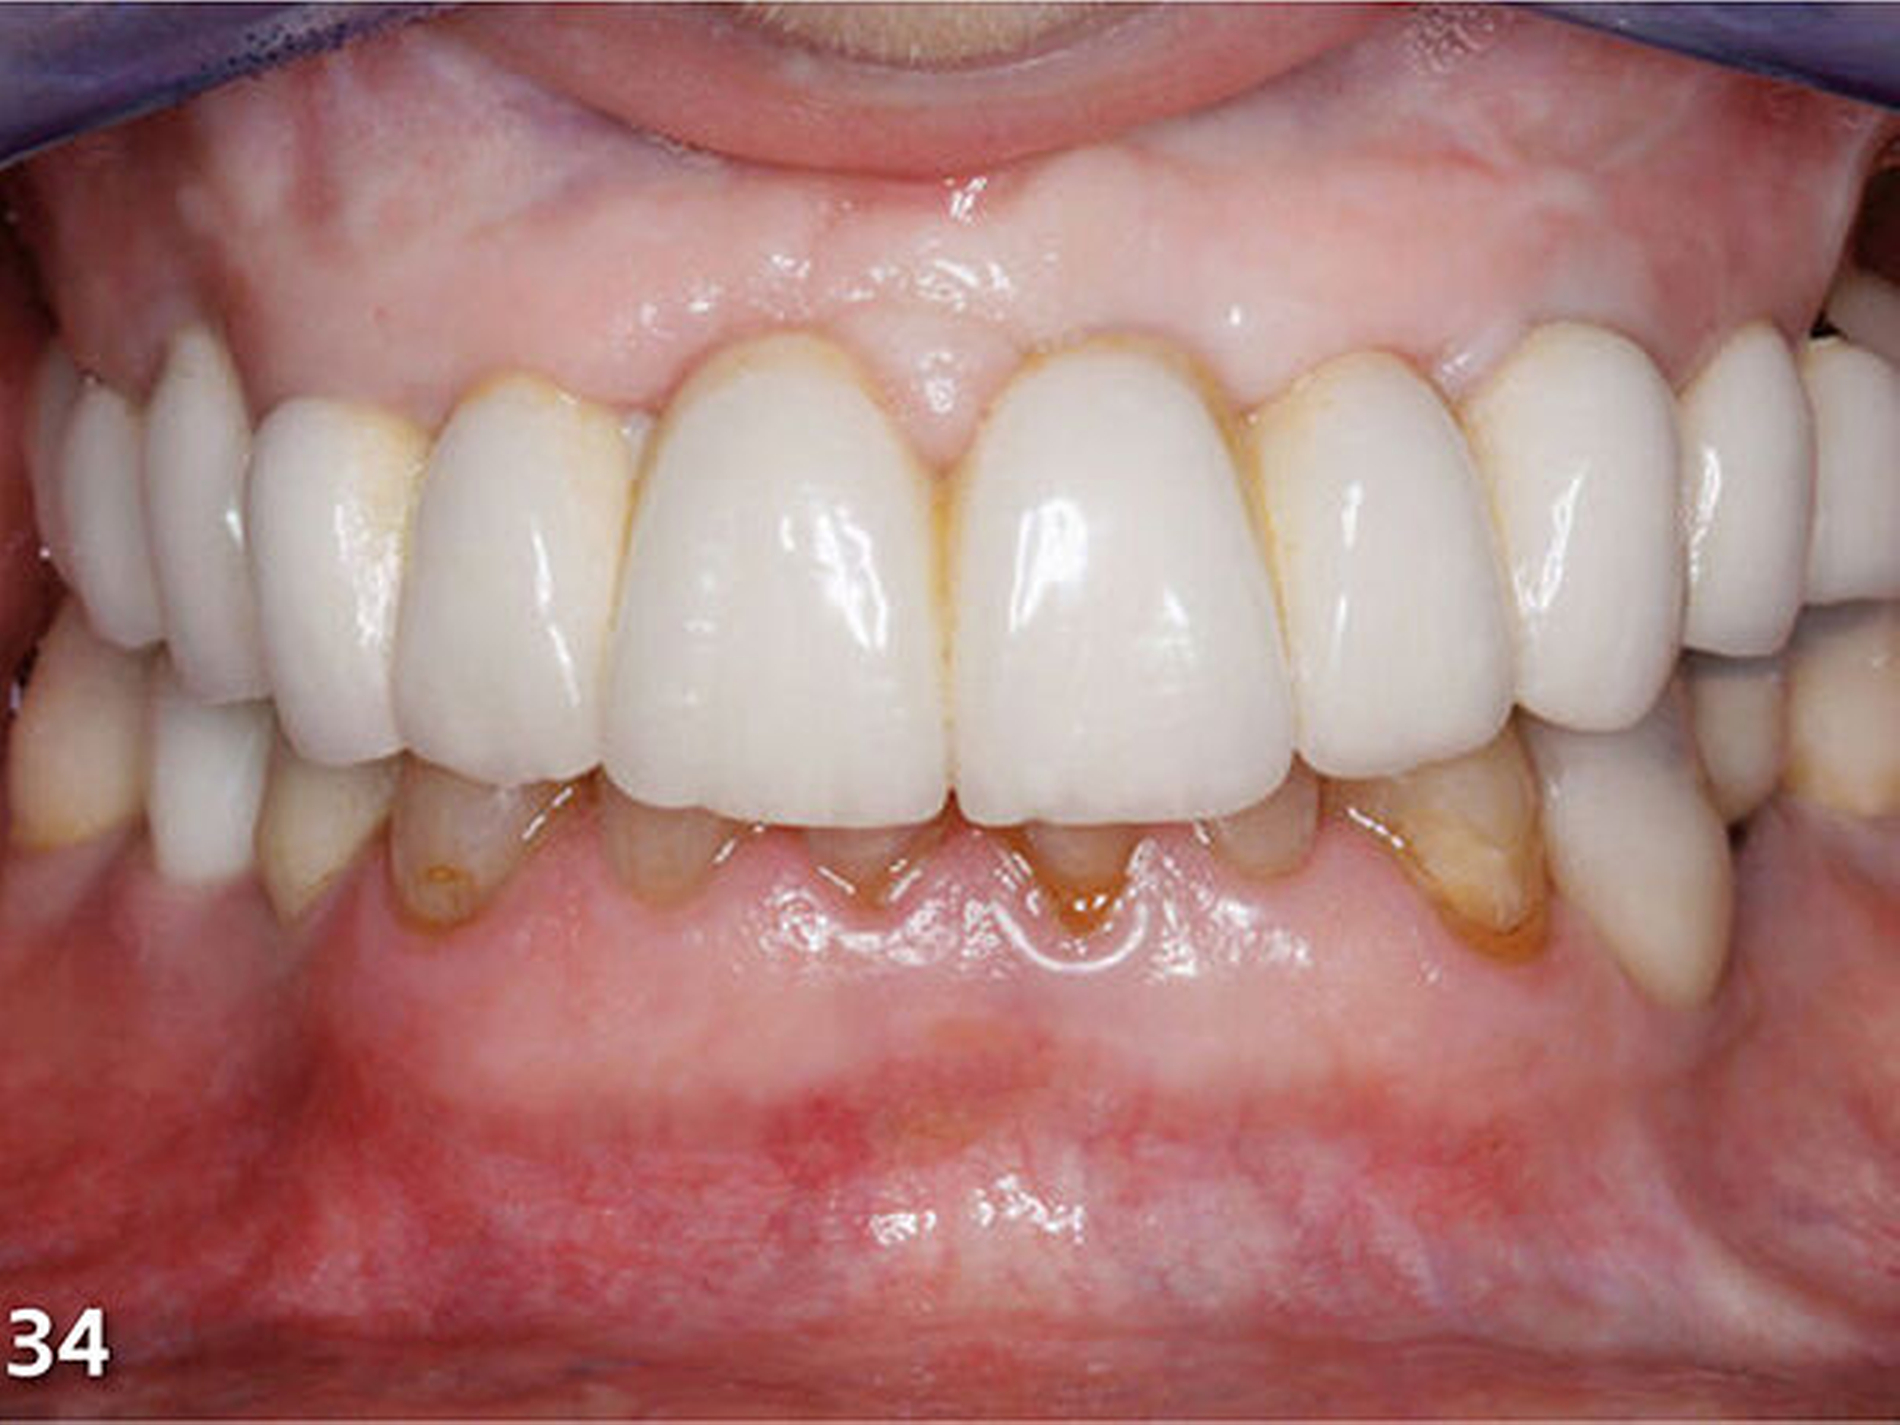

Nach dem Ausarbeiten und Polieren sämtlicher Restaurationen (Abb.31 und 32) wurden die statische und die dynamische Okklusion nochmals kontrolliert; es zeigte sich eine gute Übereinstimmung mit dem okklusalen Kontaktmuster aus dem Wax-up (Abb.33). Da sämtliche Restaurationen ohne Verabreichung von Lokalanästhesie aufgebaut wurden, konnte die Patientin sofort nach Abschluss der Behandlung, nach einer kurzen Phase der Lockerung der Kaumuskulatur, ein erstes positives Feedback zur neuen Unterkieferposition geben (Abb.34 und 35).